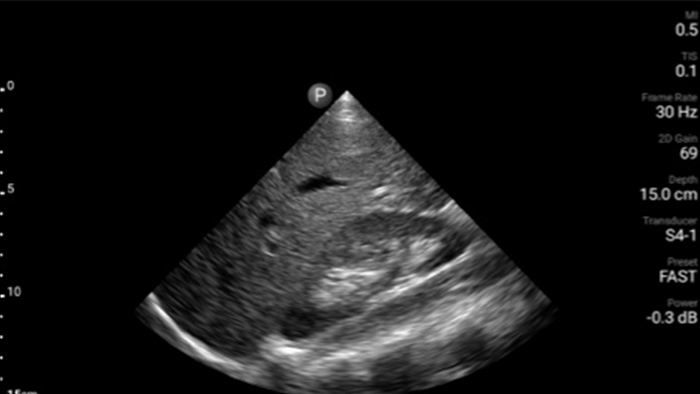

Exceptional ultrasound imaging

Lumify handheld ultrasound offers images that enhance diagnostic confidence.